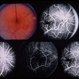

- Cryptococcus

- cryptococcus, meningitis

- 60-year-old male, III cryptococcus meningitis, 20/32 OU (AIDS).